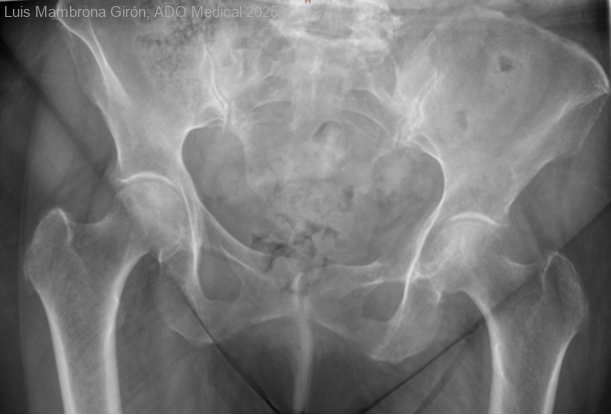

Abordaje complejo en neoplasia pélvica ósea

Mujer de 74 años que hace seis inicia cuadro de lumbalgia/coxalgia izquierda. Es valorado por traumatología que orienta el caso como artralgia mecánica inespecífica. La clínica mejora parcialmente con tratamiento analgésico antiinflamatorio. Dos años más tarde, presenta...